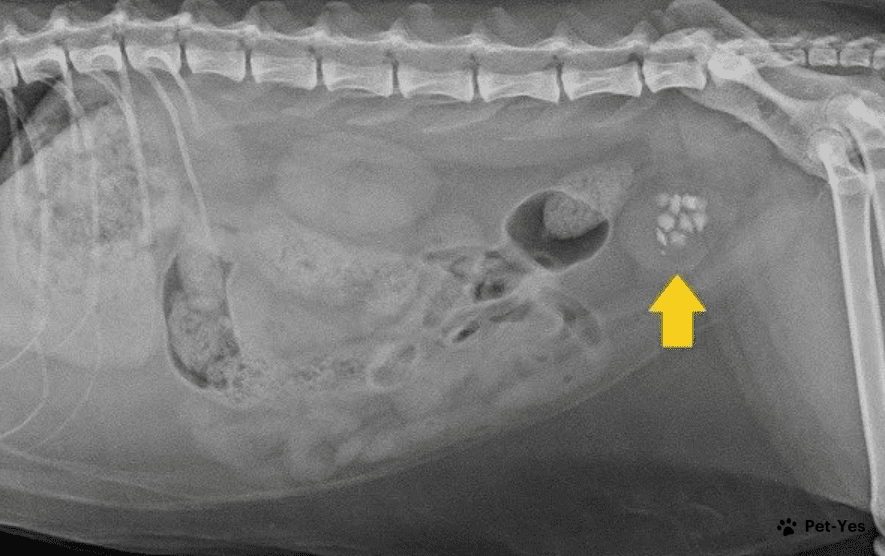

Мочекаменная болезнь — это одно из самых распространенных заболеваний у домашних кошек. Она заключается в образовании солевых отложений, таких как песок и камни, в мочевыводящих путях. В этой статье я опишу, почему возникает это заболевание и как с ним бороться. Камни и песок в мочевом пузыре образуются из различных веществ, которые обычно выводятся с мочой. Однако, когда их количество становится слишком большим или нарушаются какие-либо функции организма, они не растворяются и оседают, образуя осадок, который может превратиться в камни.

Камни и песок в мочевом пузыре образуются из различных веществ, которые обычно выводятся с мочой. Однако, когда их количество становится слишком большим или нарушаются какие-либо функции организма, они не растворяются и оседают, образуя осадок, который может превратиться в камни.

Мочекаменная болезнь может проявляться в двух формах: образованием струвитов (при щелочном pH) и оксалатов (при кислой среде). Струвиты можно растворить медикаментами, а вот оксалаты часто требуют хирургического вмешательства.